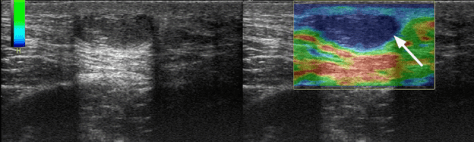

Ультразвукове дослідження молочних залоз виконується з метою виявлення доброякісних або злоякісних пухлин, запального процесу (мастити, абсцеси), фіброзно-кістозної мастопатії та оцінки стану прилеглих лімфатичних вузлів. Дослідження проводиться з застосуванням кольорового доплера та Еластографії. Під час і після дослідження лікар пояснює пацієнту виявлені ознаки, що будуть відображені в діагностичному висновку лікаря.

При виявленні будь-яких утворень в молочних залозах додатково проводиться Еластографія – нова технологія ультразвукового дослідження, яка дозволяє оцінити еластичність новоутворень і допомагає відрізнити доброякісні від злоякісних пухлин: щільні, жорсткі утворення при еластографії мають синій колір і найчастіше представлені злоякісними пухлинами, в той час як еластичні, м’які утворення на еластографії мають зелений колір, з жовто-червоним забарвленням і найчастіше представлені доброякісними утвореннями. Еластографія підвищує точність діагностики і може знижувати відсоток непотрібних біопсій молочних залоз.